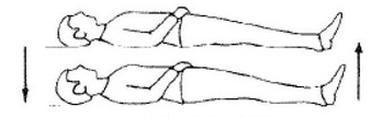

Którą z zasad pięciu zmian stosowanych w technice pracy na cztery ręce przedstawia rysunek?

A. IV

B. III

C. II

D. I